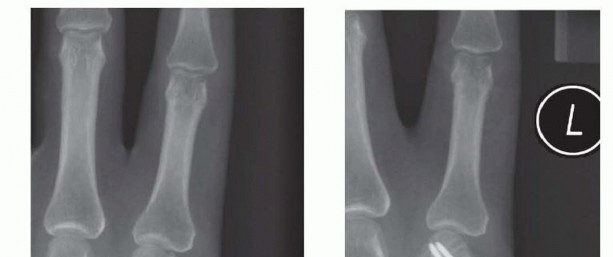

Clinical & Radiographic Imaging Archive